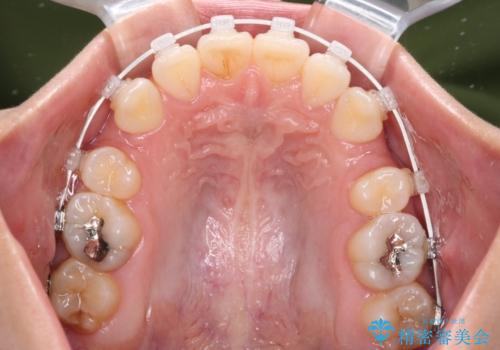

- 矯正装置

- 審美装置

奥歯の咬み合わせが理想的であり、歯の移動に時間のかかる出っ歯でもなかったため、2年程度で治療を終えることを目標としましたが、無事に予定通りの2年間で終えることができました。